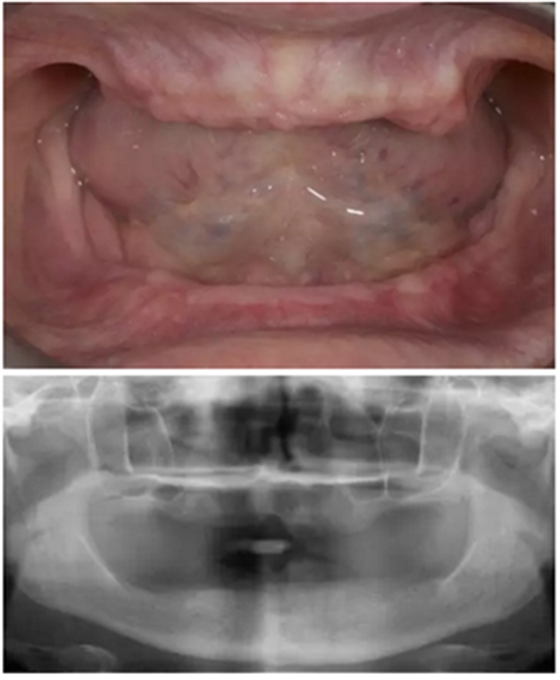

病人情況:62歲女性,殘齒拔出后2個月,不接受植骨手術(shù)。

拔除所有牙后兩個月愈合,在愈合期間,患者佩戴治療性義齒以恢復(fù)顳下頜關(guān)節(jié)和重建自然面型的垂直距離。上下頜骨吸收趨于穩(wěn)定,該患者拒絕任何骨增量手術(shù)并要求最低程度的侵入性創(chuàng)傷患者最關(guān)注的是最終修復(fù)的效果,不僅要恢復(fù)自然的美觀和功能,還要求有充足的唇頰支撐和漂亮的微笑設(shè)計。